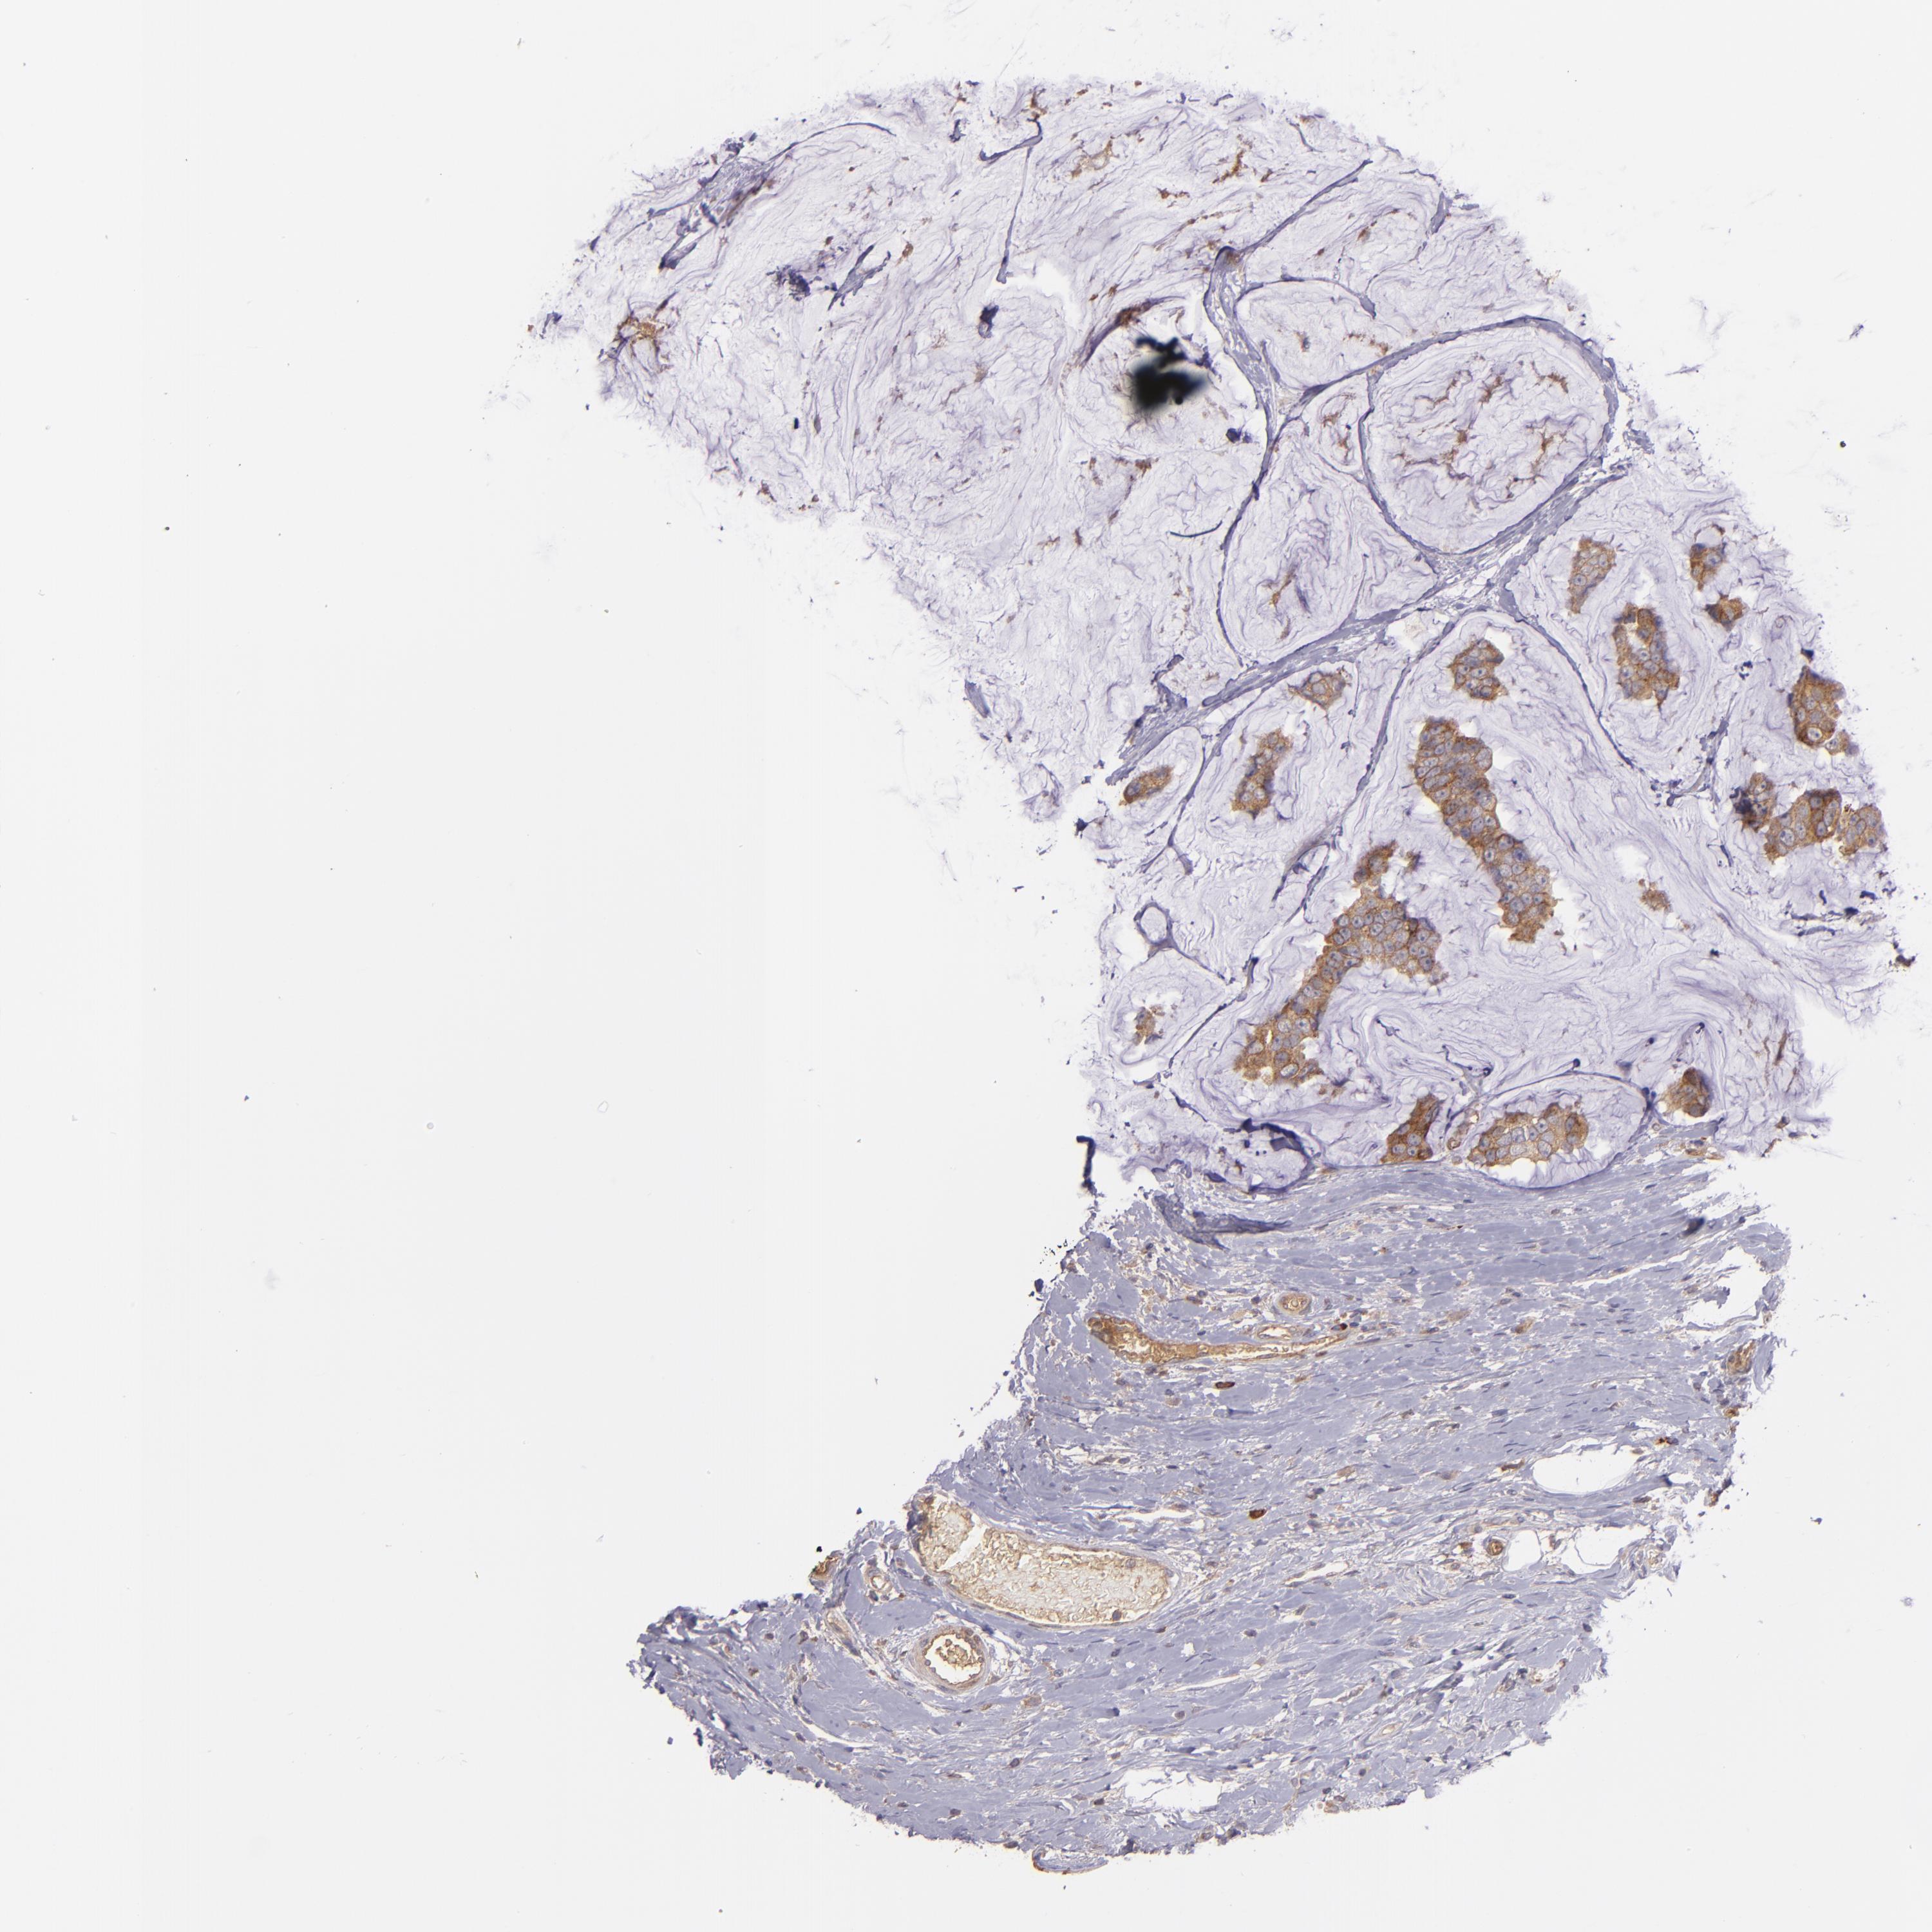

CANCER BREAST CANCER Show tissue menu

BRCA TCGA BRCA VALIDATION PROTEIN EXPRESSION